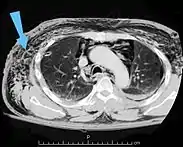

| An abdominal CT scan of a patient with subcutaneous emphysema (arrows) | |

Significant cases of subcutaneous emphysema are easy to diagnose because of the characteristic signs of the condition.[1] In some cases, the signs are subtle, making diagnosis more difficult.[13] Medical imaging is used to diagnose the condition or confirm a diagnosis made using clinical signs. On a chest radiograph, subcutaneous emphysema may be seen as radiolucent striations in the pattern expected from the pectoralis major muscle group. Air in the subcutaneous tissues may interfere with radiography of the chest, potentially obscuring serious conditions such as pneumothorax.[18] It can also reduce the effectiveness of chest ultrasound.[27] On the other hand, since subcutaneous emphysema may become apparent in chest X-rays before a pneumothorax does, its presence may be used to infer that of the latter injury.[13] Subcutaneous emphysema can also be seen in CT scans, with the air pockets appearing as dark areas. CT scanning is so sensitive that it commonly makes it possible to find the exact spot from which air is entering the soft tissues.[13] In 1994, M.T. Macklin and C.C. Macklin published further insights into the pathophysiology of spontaneous Macklin's Syndrome occurring from a severe asthmatic attack.